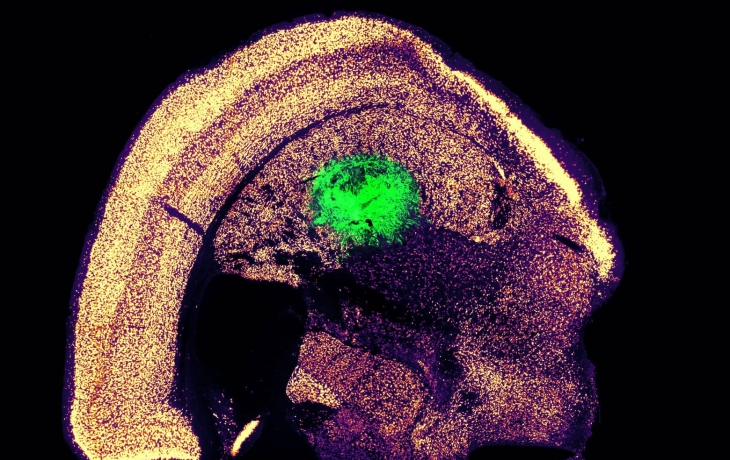

Исследователи Массачусетского технологического института разработали эффективный метод прямого преобразования клеток кожи в нейроны, минуя стадию стволовых клеток...